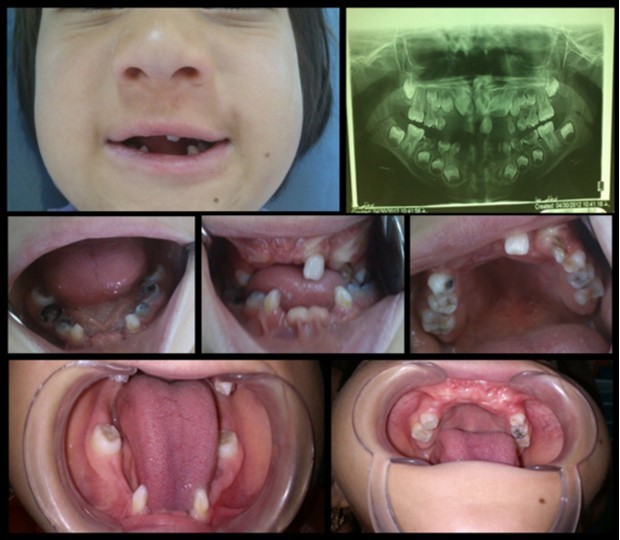

The mandibular and maxillary incisors were absent (excluding upper left lateral maxillary incisor which was loose) mandibular deciduous molars, right maxillary first deciduous molar and left deciduous maxillary canine had severe decay and the right maxillary permanent canines were erupting. Multiple frenulum and attaching labial mucosa to alveolar mucosa were also observed (Figure 2).

In Radiographic examination of tooth, maxillary incisor tooth germs were absent and all of the four “second permanent molars” were un-erupted and root of primary mandibular canines have severe mesial curve (Figure 2).

Figure 2.Intra oral photographs and panoramic radiograph: anodontia of mandibular and maxillary incisors, absence of mucobuccal fold in maxillary and mandibular anterior region, congenital absence of the incisors, conical shaped teeth and multiple frenula.

Intra oral photographs and panoramic radiograph: anodontia of mandibular and maxillary incisors, absence of mucobuccal fold in maxillary and mandibular anterior region, congenital absence of the incisors, conical shaped teeth and multiple frenula.